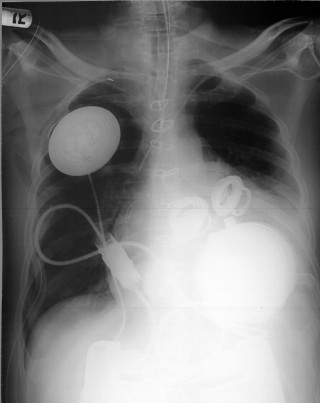

The AbioCor is the world's first completely self-contained replacement heart. A product of three decades of research, development and testing, the AbioCor is central to ABIOMED's mission to make real the day when heart failure need not mean the end of life or the ability to enjoy life. Designed to fully sustain the body's circulatory system, the AbioCor is intended for end-stage heart failure patients whose other treatment options have been exhausted. A rechargeable internal battery allows the patient to be completely free of the external power transmission unit for some period of time. Normally an external power pack transmits power across the skin.

The AbioCor System consists of the following implanted components:

- Replacement Heart

- Implanted TET

- Implanted Controller

- Implanted Battery

- Implanted Cable

In addition to the implanted components, the AbioCor System has external components that provide power to the AbioCor System.

1. Surgeons implant the energy-transfer coil in the abdomen.

2. The breast bone is opened and the patient is placed on a heart-lung machine.

3. Surgeons remove the right and left ventricles of the native heart. They leave in the right and left atria, the aorta and the pulmonary artery. This part of the surgery alone takes two to three hours.

4. Atrial cuffs are sewn to the native heart's right and left atria.

5. A plastic model is placed in the chest to determine the proper placement and fit of the heart in the patient.

6. Grafts are cut to an appropriate length and sewn to the aorta and pulmonary artery.

7. The AbioCor is placed in the chest. Surgeons use "quick connects" -- sort of like little snaps -- to connect the heart to the pulmonary artery, aorta and left and right atria.

8. All of the air in the device is removed.

9. The patient is taken off the heart-lung machine.

10. The surgical team ensures that the heart is working properly.